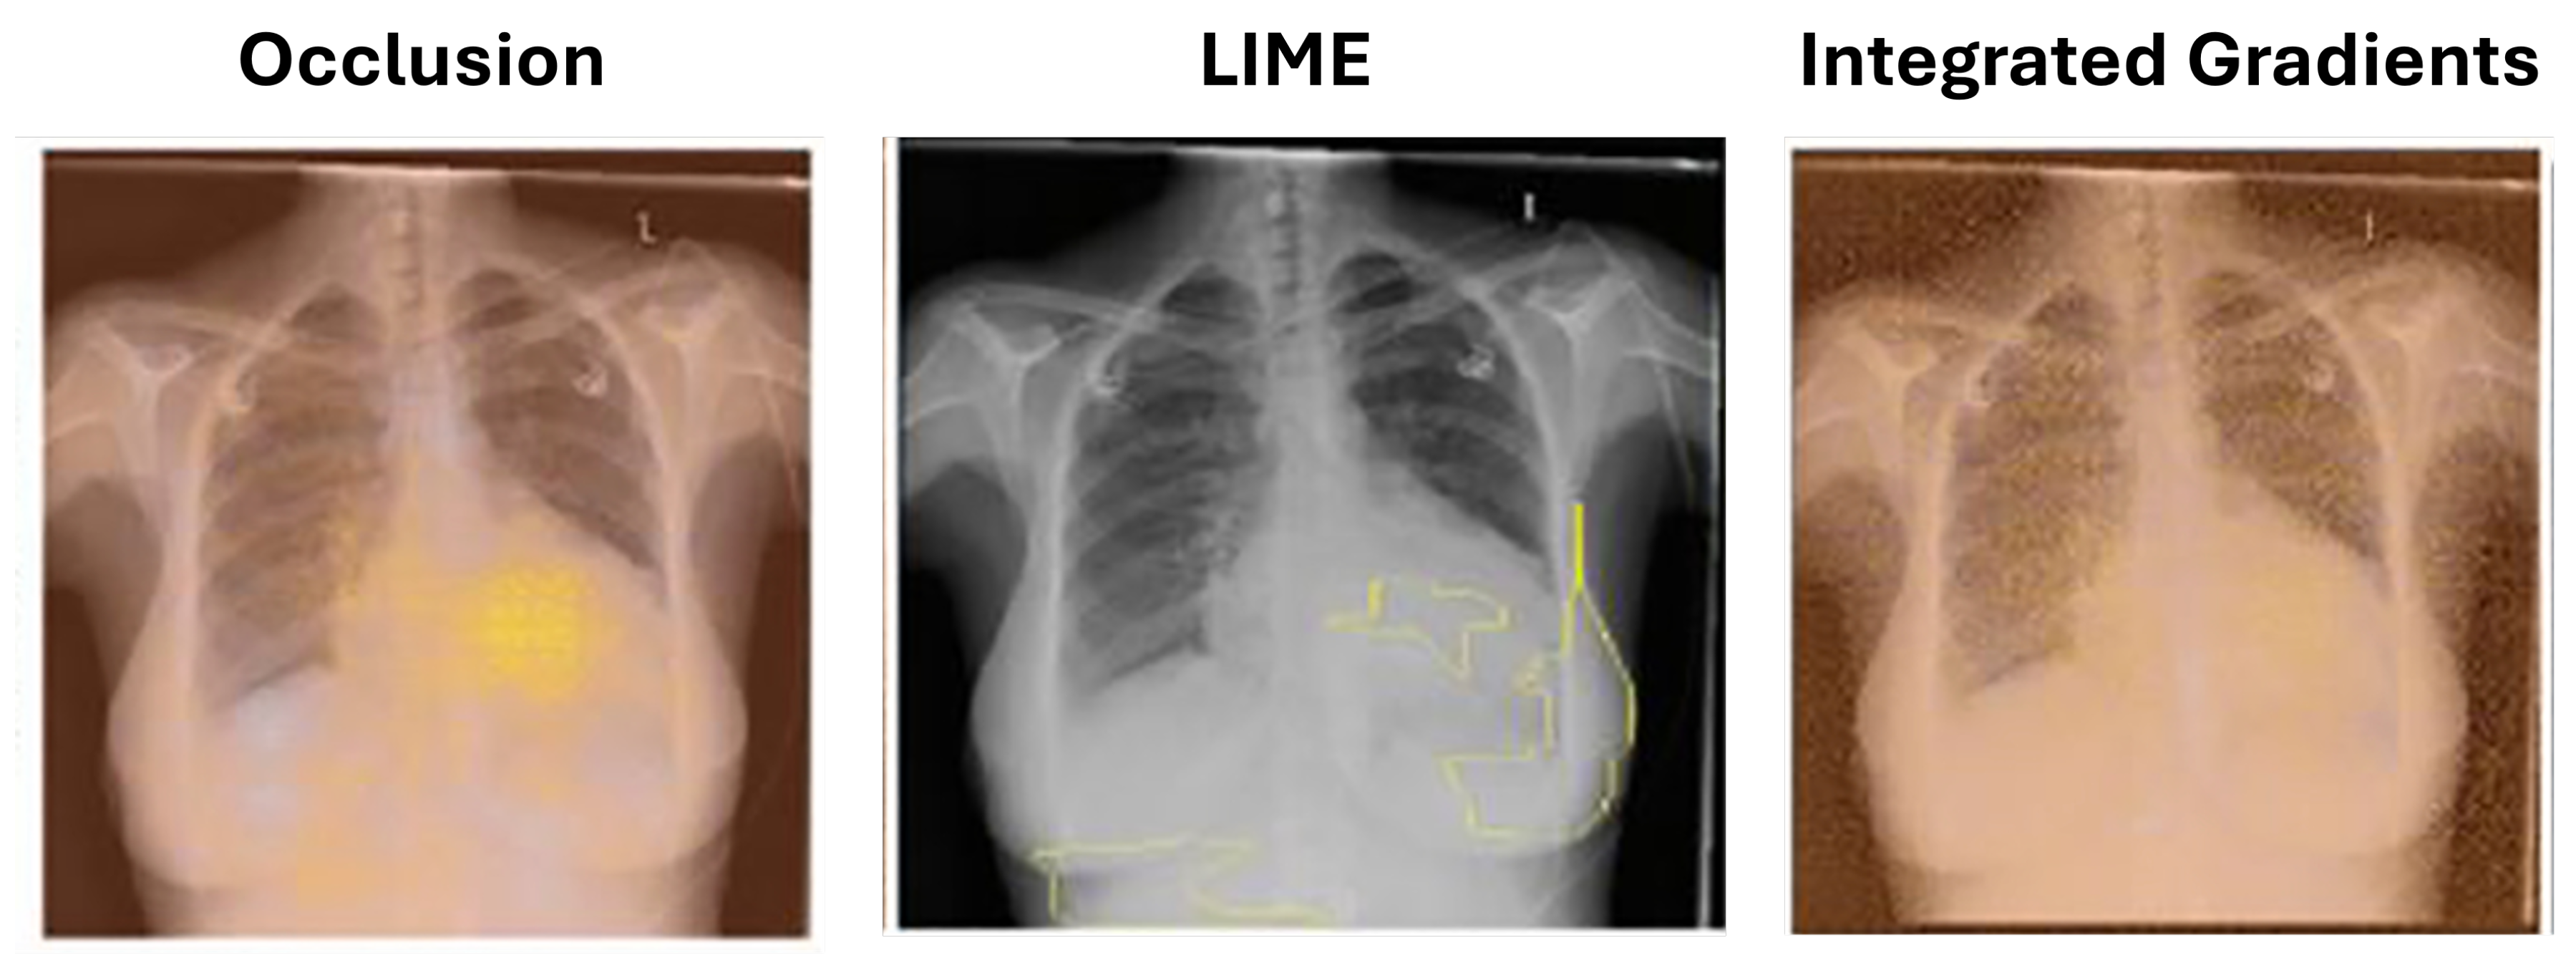

5.1.1. Occlusion

5.1.2. Local Interpretable Model-Agnostic Explanations (LIME)

5.1.3. Integrated Gradients

| Chest | Classification | X-ray | AUC: 82.0% | OS, IG, LIME | [43] |